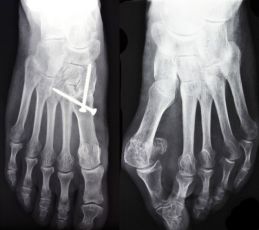

Hallux valgus OP vorher nachher

Für Patienten sind vorher nachher Fotos einer Hallux valgus Operation sehr hilfreich, da sie eine Vorstellung geben, wie ein Ergebnis nach einer Hallux valgus Operation aussehen kann.

Auf dem Foto „Hallux valgus vor OP“ ist eine typische beidseitige Fehlstellung am Großzehengrundgelenk zu sehen. Sie ist am rechten Fuß stärker ausgeprägt ist als am linken. Beim rechten Fuß weicht der Großzeh deutlich zur Seite ab, während sich der Mittelfußknochen nach medial (nach innen) verschiebt und so den prominenten Ballen entstehen lässt.

Auf dem Foto „Hallux valgus vor und nach OP“ ist der rechte Fuß bereits operiert und zeigt ein korrigiertes Bild nach einer knöchernen Umstellungsoperation. Der Vergleich von vorher und nachher zeigt klar die Wiederherstellung einer harmonischen Fußform mit geradem Großzeh und einem deutlich vermindertem Ballenvorsprung am rechten Fuß. Für den Ballenzeh am linken Fuß ist die Hallux valgus Operation sechs Monate nach der ersten Hallux OP geplant.